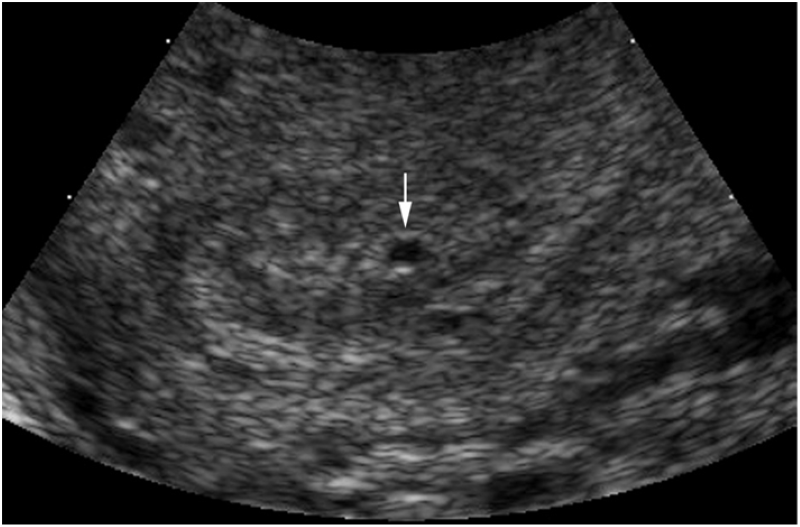

Bệnh lý tim mạch

Đau ngực trái, bệnh mạch vành (sau đặt stent, sau mổ bắc cầu);Tăng huyết áp;

Chẩn đoán các bệnh tim bẩm sinh ở người lớn và trẻ nhỏ;

Bệnh mạch vành

Khám, phát hiện, tư vấn, theo dõi và điều trị các bệnh lý bệnh mạch vành.